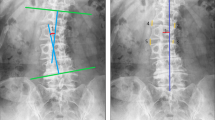

Lateral vertebral translation was classified into two conditions: “yes” was the presence of a lateral vertebral translation of > 3 mm; otherwise, it was “no.” Apical vertebral rotation was classified into five grades according to Nash–Moe method [11] (if the apex was disk, the apical vertebra was under the apex): Grade 0: convex and concave no asymmetry; Grade 1: convex migrates within first segment and concave may start disappearing; Grade 2: convex migrates to second segment and concave gradually disappears; Grade 3: convex migrates to middle segment and concave is not visible; and Grade 4: convex migrates past midline to concave side of vertebral body and concave was not visible. Grade 4 was less common, so we merged Grade 4 and Grade 3 into Grade 3 (Fig. 1).

Male, 75Y, degenerative lumbar scoliosis: a showing that apical vertebrae was L3 vertebrae and its rotation belonged to Grade 2, no lateral translation; lumbar scoliosis Cobb’s angle was 21.2°; Main curve was located on lumbar segment with left scoliosis, and compensatory curve whose orientation was contrary to main curve was located on lumbosacral segment; b showing that lordotic angle was 41.1°